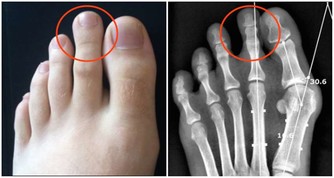

血糖高的人,多飲、多尿是他們的最典型的症狀,據此就能準確判斷出是否是糖尿病患者。

可如果哪天他們的飲水次數、排尿次數,甚至於尿液的氣味,都發生了變化,和正常人保持在同一個水平線上。

那麼,一定要誇獎他們,血糖控制的真不錯。